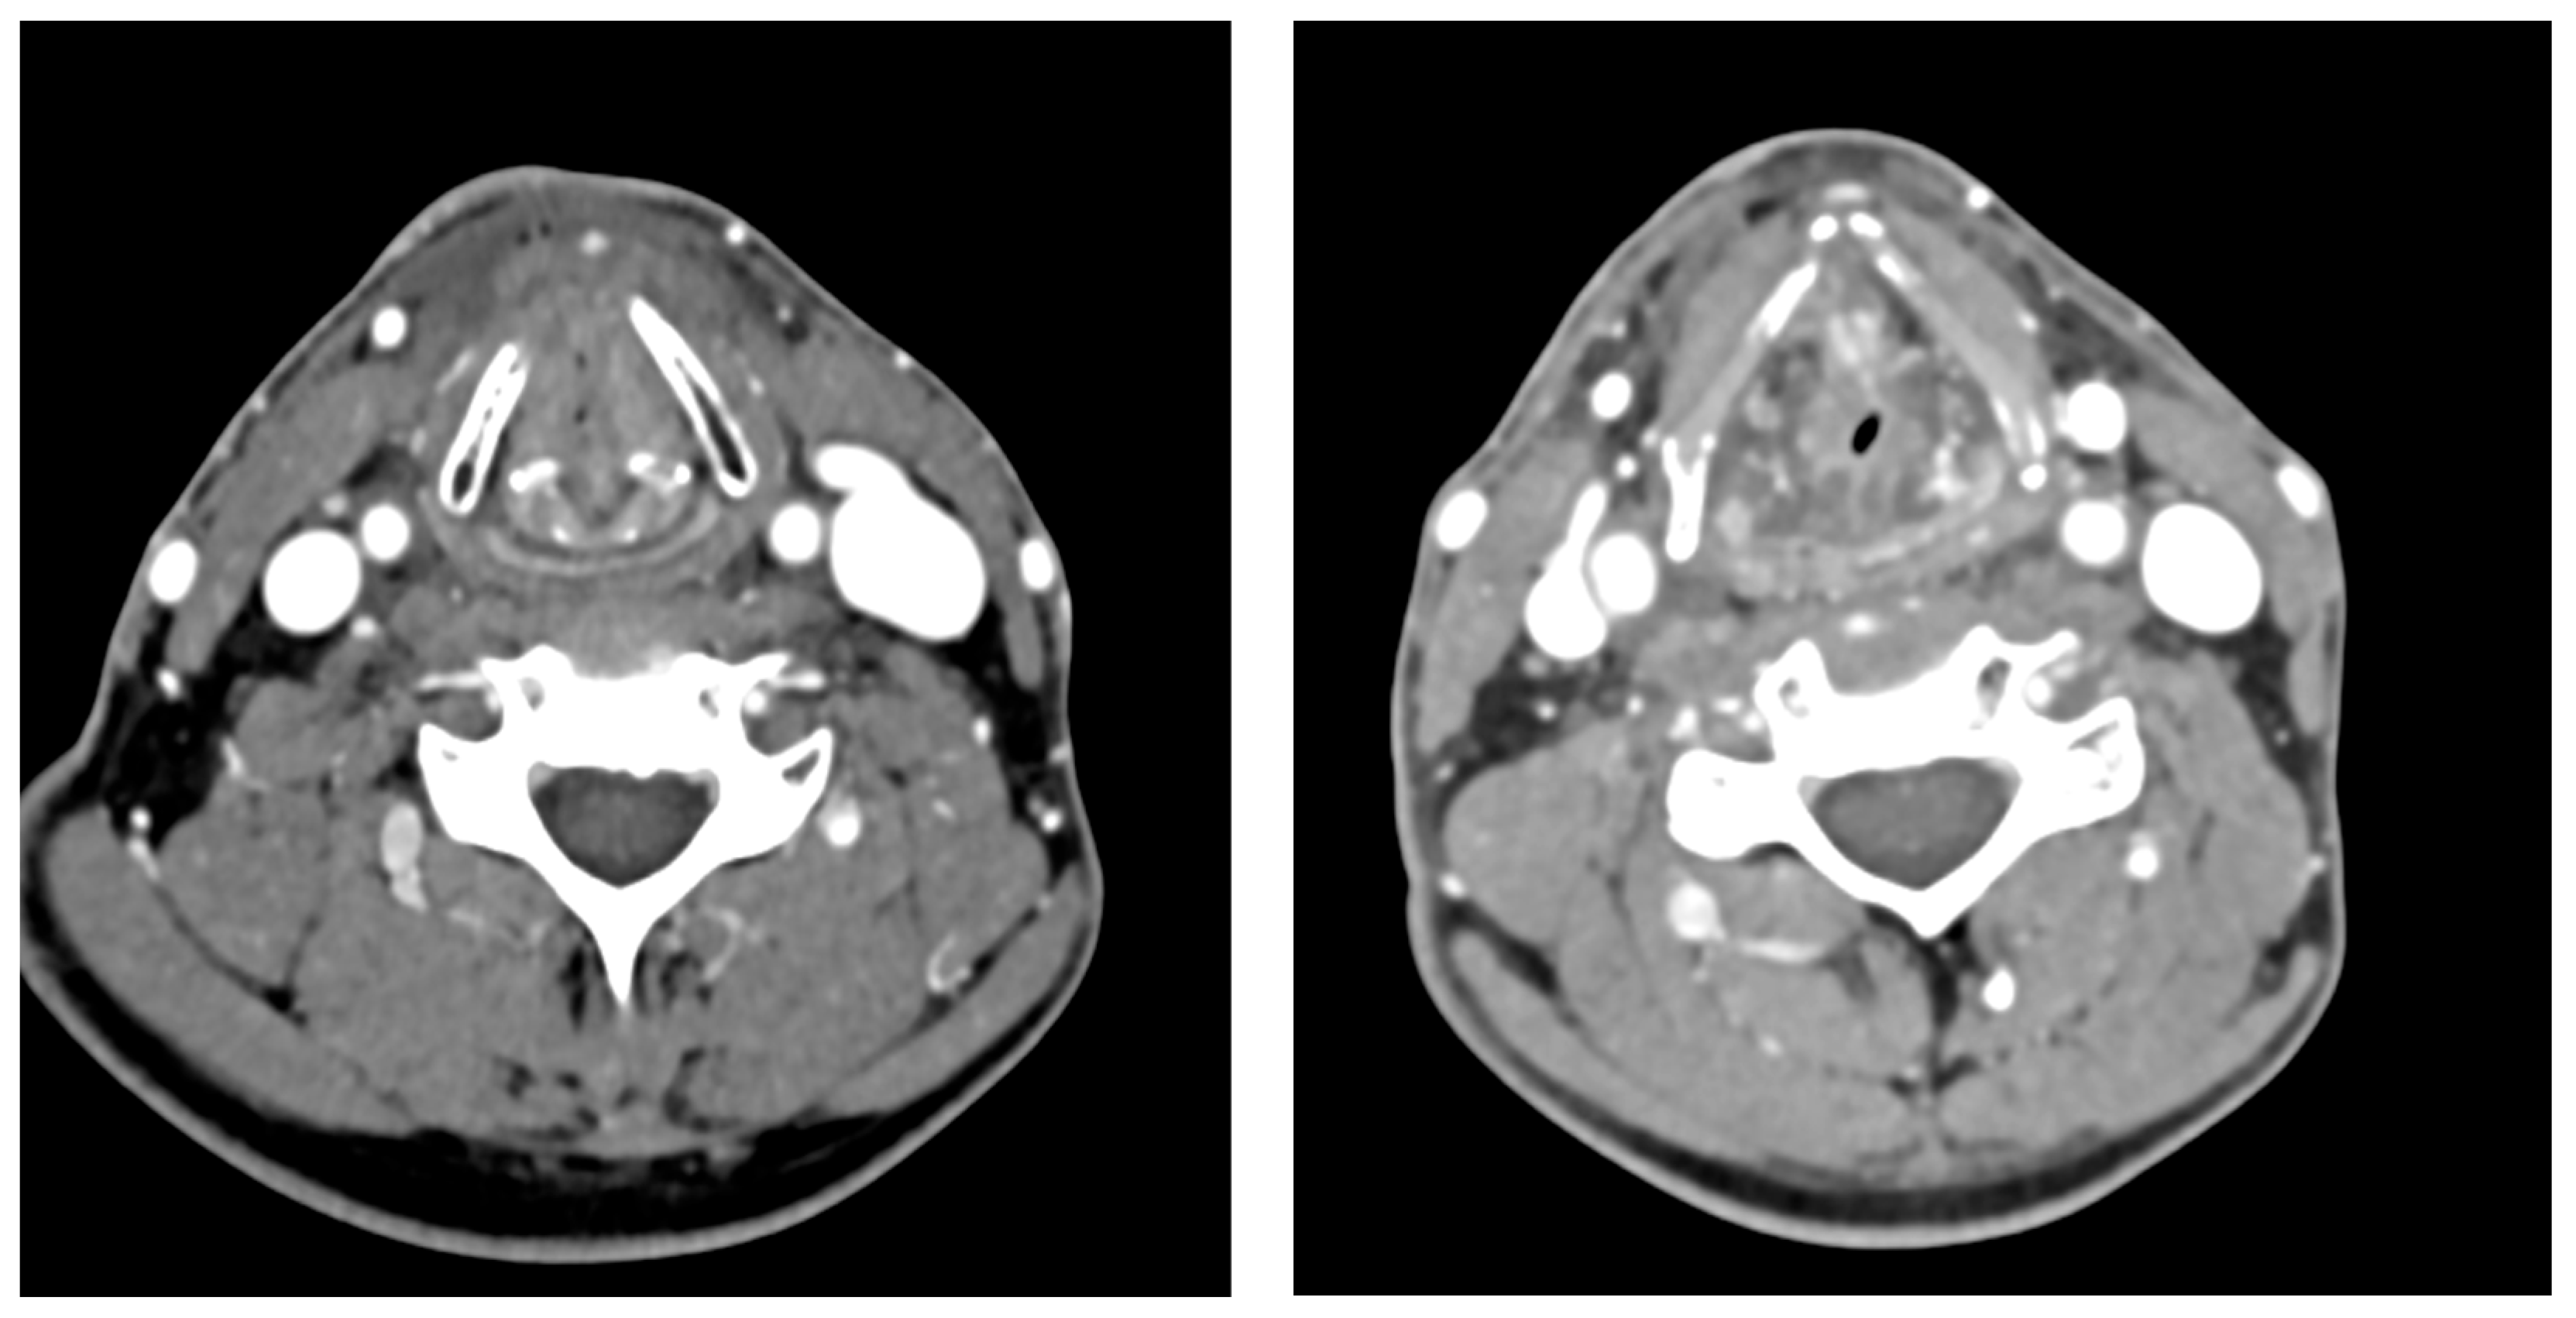

2. Case Presentation